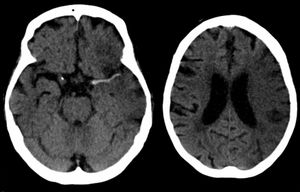

뇌졸중은 신경학적 검사(예: NIHSS) , CT 스캔(대부분 조영제 증강 없이), MRI 스캔, 도플러 초음파, 혈관조영술 등 여러 가지 방법으로 진단한다. 뇌졸중 자체의 진단은 영상 기술의 도움을 받아 임상적으로 이루어지며, 영상 기술은 뇌졸중의 아형과 원인을 결정하는 데에도 도움이 된다.[74] 뇌졸중 진단을 위한 혈액 검사는 아직 일반적이지 않지만, 혈액 검사는 뇌졸중의 원인을 파악하는 데 도움이 될 수 있다.[74] 사망한 사람의 경우 뇌졸중 부검을 통해 뇌졸중 발생 시점과 사망 시점 사이의 시간을 확인할 수 있다.

뇌졸중은 신경학적 검사(예: NIHSS) , 컴퓨터 단층촬영(CT) (대부분 조영제 증강 없이), 자기공명영상(MRI) 스캔, 도플러 초음파, 및 혈관조영술 등 여러 가지 방법으로 진단됩니다. 뇌졸중 자체의 진단은 영상 기술의 도움을 받아 임상적으로 이루어집니다. 영상 기술은 뇌졸중의 아형과 원인을 결정하는 데에도 도움이 됩니다.[74]

응급 상황에서 허혈성 뇌졸중(혈관이 막혀서 발생)과 출혈성 뇌졸중(혈관이 터져서 발생)을 진단하기 위해 CT와 MRI가 사용됩니다.

MRI는 만성 출혈을 감지하는 데 더 민감합니다.[76] CT는 특히 뇌졸중이 작거나, 최근에 발생했거나,[12] 뇌간이나 소뇌 부위(후순환 뇌경색)에 있는 경우 허혈성 뇌졸중을 감지하지 못할 수 있습니다. MRI는 확산 강조 영상을 사용하여 후순환 뇌경색을 감지하는 데 더 효과적입니다.[77] CT는 특정 뇌졸중 모방 질환을 배제하고 출혈을 감지하는 데 더 많이 사용됩니다.[12]